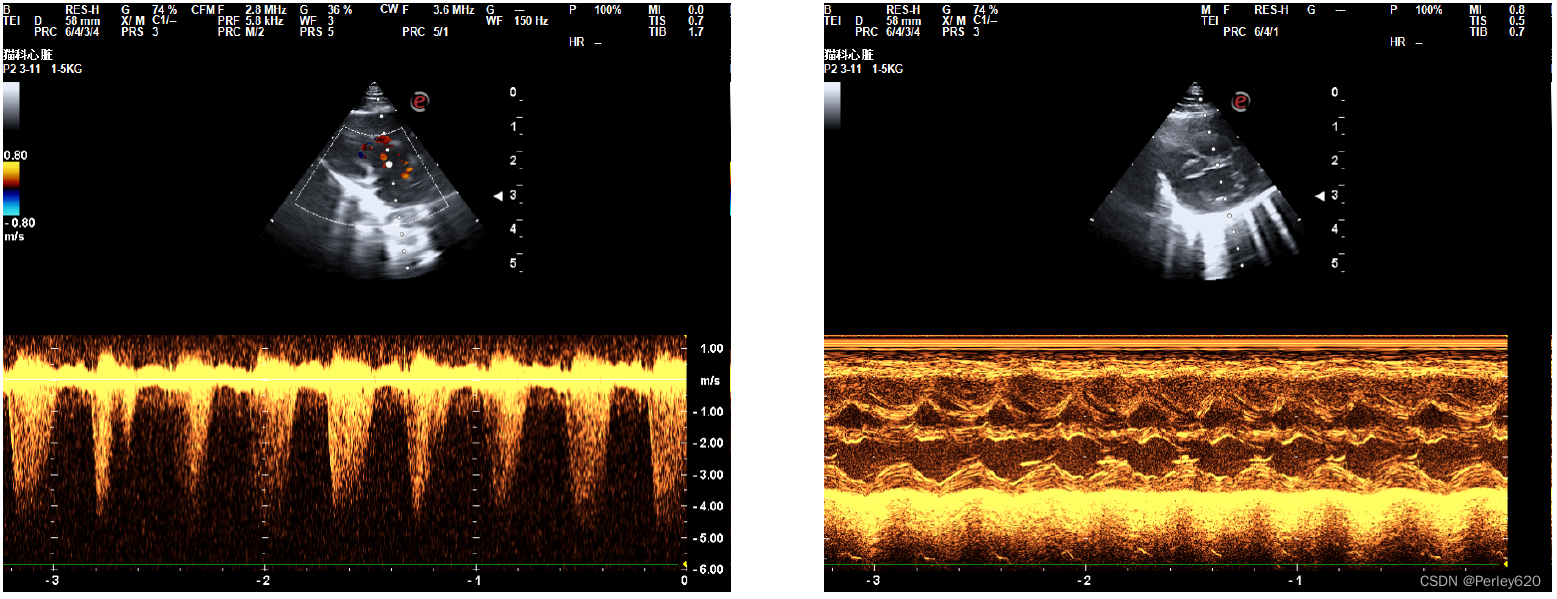

然后给她拍X光片,给她做彩超看心脏,宠物医院的院长看了半天,也没能确定是什么问题,她觉得是心脏左心室隔膜缺损,但没法给定论。

我们就去了宠物医院的总院,找了总院的院长做进一步的检查,最终是重度肺高压,就是很严重的一种病。

诊断的B超图